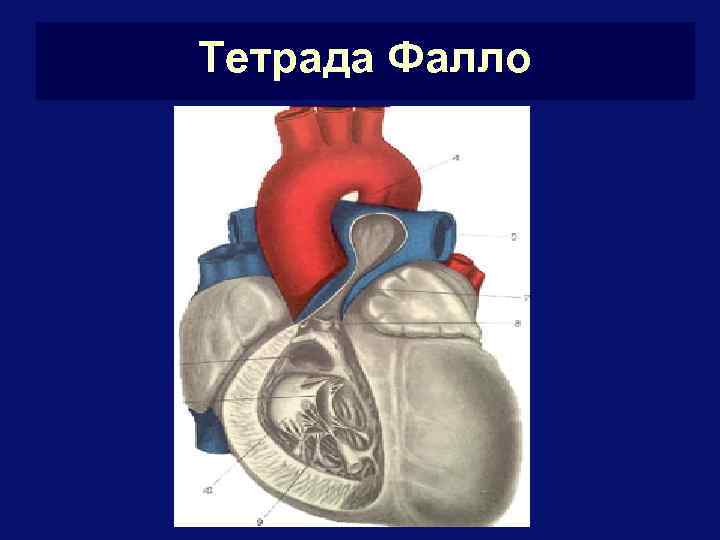

Тетрада Фалло

Тетрада Фалло § § Включает: стеноз выходного отдела Пж + большой ДМЖП + аорту-наездник над ДМЖП + гипертрофию Пж Нарушения гемодинамики обусловлены степенью стеноза Ла и ДМЖП. Чем резче стеноз, тем хуже прогноз При выраженном стенозе шунтирование идет справа-налево (у 80%), при незначительном – слева-направо Неблагоприятный прогноз обусловлен артериальной гипоксемией и облитерацией легочных капилляров (из-за гиповолюмии малого круга)